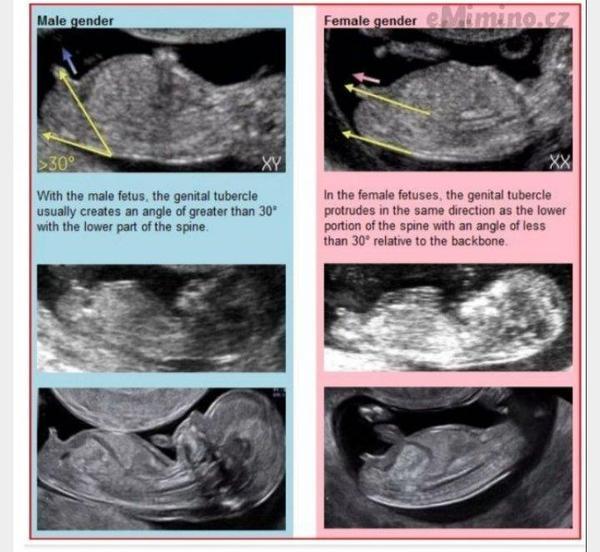

- Určení pohlaví z ultrazvuku v 12.–14. týdnu se v praxi provádí podle sklonu pohlavního hrbolku ("nub sign"): když hrbolek směřuje nahoru, lékaři to interpretují jako kluka, když je rovnoběžně se zakřivením páteře nebo dolů, jako holku.

- Určování pohlaví podle pohlavního hrbolku (nub sign) kolem 12.–14. tt je v praxi běžné, ale není stoprocentní.

No kdyz je rovne nebo spis dolu je to holcicka a kdyz nahoru jakoby trci tak pry kluk.

Já nevím, ale tady ti to těžko řekne někdo přesněji než zkušená gynekoložka. Na 95% ti řekne, že to bude holka, tak nevím jestli to jen chceš potvrdit? Nicméně k tvému dotazu (taky nemám ráda, když někdo komentuje něco úplně mimo mísu 😁). Když to porovnáš tady s těmi ukazkovými UZ, tak tam taky vidím holku. Záleží na úhlu toho hrbolku.

@fabu1ous řekla bych holčička, ale v tomto týdnu se teprve začíná vyvíjet pohlaví. Sestřenici tvrdili holčičku do 20tt, pak o týden později byl klouček, teď mu jsou dva měsíce 😉 takže bych s verdiktem pohlaví počkala na druhý screening. Nám řekli kluka v 16tt, ale přeci jen pytlík i pindík jdou vidět lépe 😀